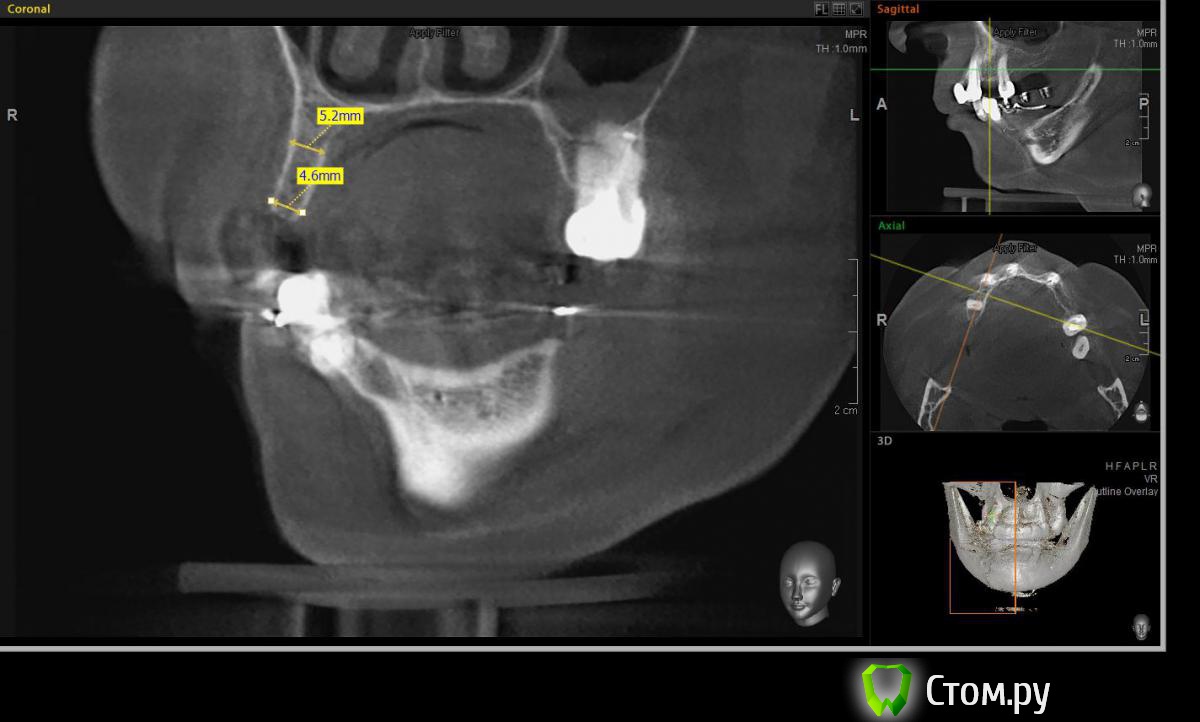

Евгений Ходыкин Опубликовано 22 июля, 2014 Автор Поделиться Опубликовано 22 июля, 2014 Дабы не плодить тем решил очередной случай выложить сюда Решили с пациенткой пока начать с в.ч. В планах имплантация в область отсутствующих 1.6, 1.4, 1.2, 2.1, 2.2, 2.4, 2.5. С 1.6 самому более менее все понятно, мануальных навыков хватит) Прошу помощи коллег относительно остальных областей. Фронт особливо печален... Забегая наперед скажу, что блоки еще не делал. Ауто точно пока брать не планирую, ибо нет даже теоретических навыков. Хочу начать все-таки с аллоблоков. У кого какие будут мнения, заранее спасибо) Ссылка на комментарий